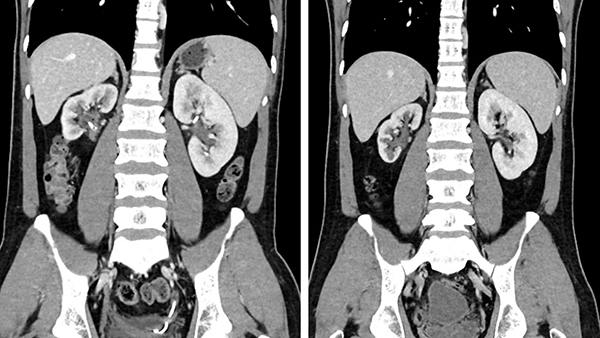

房先生治疗前后CT对比